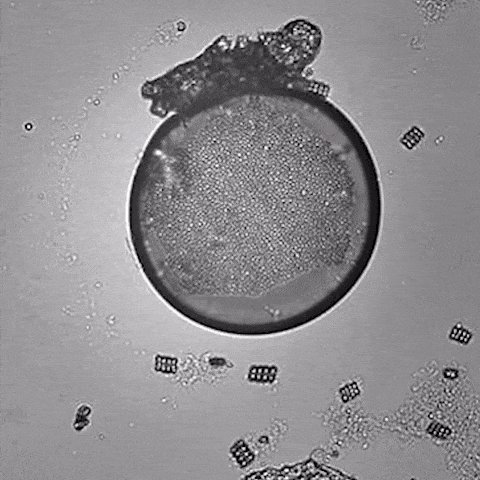

الكائنات الحَيَّة الدقيقة اختصارًا «الأَحْيَاء الدَقِيْقَة» مجموعة واسعة من الأحياء التي لا تُرى بالعين المجردة الكائنات الدقيقة تشمل البكتيريا والفطريات والطحالب

الفيروسات مفردها فيروس وتعني فيروس في اليونانية «ذيفان» أو «سم» وهو عامل ممرض صغير لا يمكنه التكاثر إلا داخل خلايا كائن حي آخر. الفيروسات صغيرة جدا ولا يمكن مشاهدتها بالمجهر الضوئي. تصيب الفيروسات جميع أنواع الكائنات الحية، من الحيوانات والنباتات اٍلى البكتيريا والعتائق.

فيه من الملايين من الأنواع المختلفة، لم يتم وصف إلا 5.000 من الفيروسات بالتفصيل، الفيروس كائن غير حي وإنما مجموعة من المكونات العضوية المعقدة تستطيع إعادة إنتاج نفسها بنفسها ملايين المرات يتكون من قشرة بروتينية داخلها حمض نووي وإنزيمات لتكراره والتحكم بجيناته